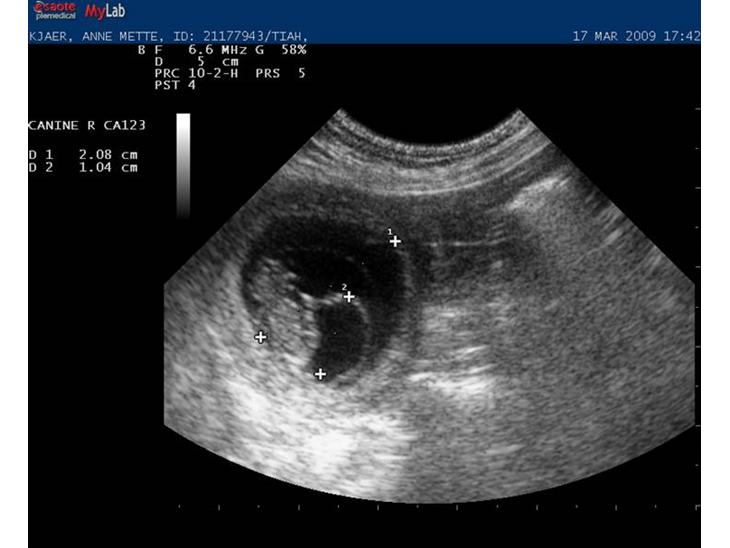

Tiahs anden scaningen paa ca. 28. dagen. der var umiddelbart 5 hvalpe at se alle med blinkende hjerter :)